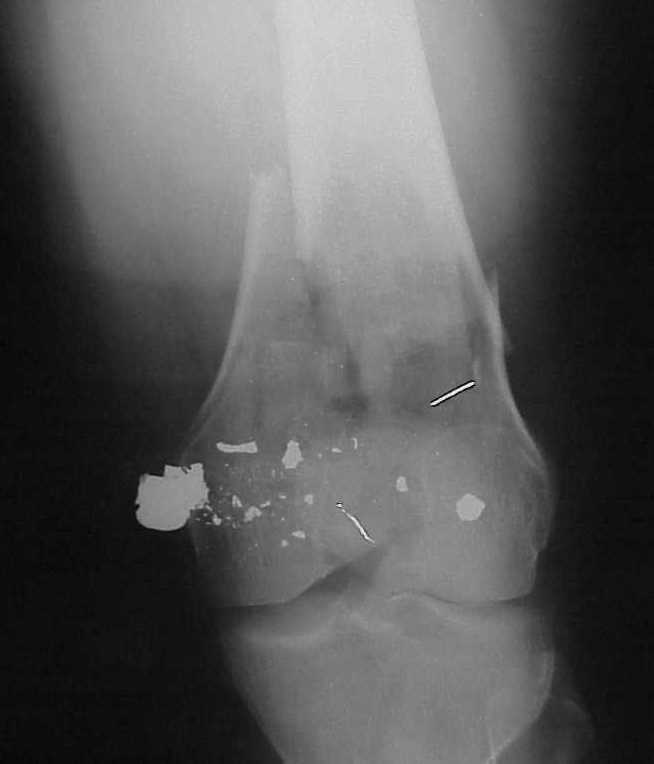

of course the only radiograms both the view of the femur (AP and LL) are not enough in order to assess the condilar ones.

So I think a TAC of the knee could be useful.

I am sure that you assessed adequately the condylar fractures, they may need fixation (eg. percutaneous screws).

A CT and knee xrays would help identify lateral condyle comminution and/or a "hoffa fragment" of the posterior condyle. I am concerned that the lateral cortex is not sufficient to give purchase for a retrograde IMN. blocking screws could improve this as a possibility. A long blade or LISS if avaible would be my secondary choices. Good luck. Any chance you can get these cases transferred earlier when it